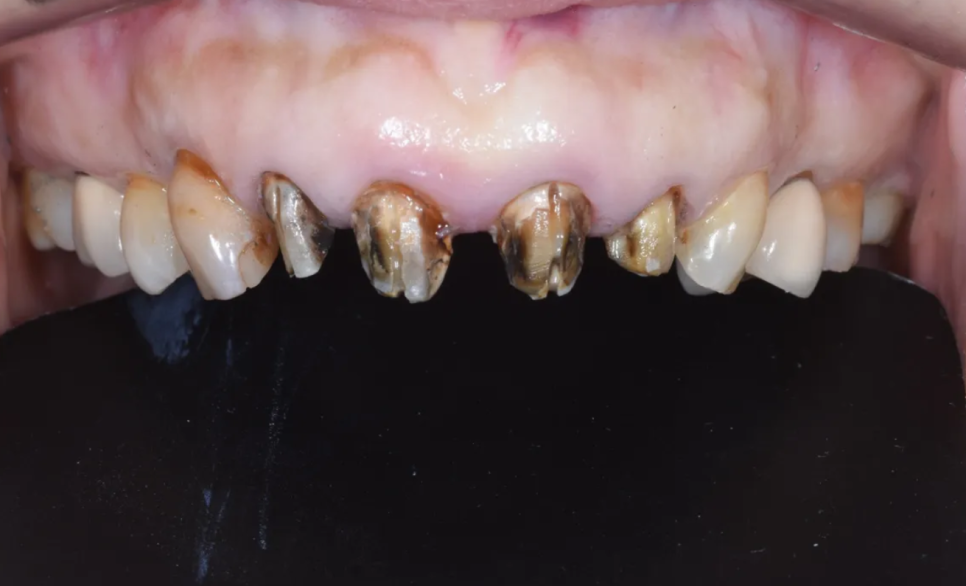

치료 과정 STEP 1 – 기존 크라운 제거 및 내부 상태 확인

먼저 오래된 PFM 크라운을 조심스럽게 제거했습니다. 크라운 아래 치아의 상태를 확인하는 이 과정이 사실 가장 긴장되는 순간이에요.

제거 후 확인한 결과, 역시나 내부 치아에 심한 변색이 있었고 2차 충치(크라운 안에서 새로 생긴 충치)도 발견되었습니다. 하지만 다행히도 포스트-코어가 탈락하거나 치아 뿌리가 깨진 상태는 아니었기 때문에, 발치 없이 치료를 이어갈 수 있었습니다.

크라운 제거 후 내부 상태 – 심한 변색과 2차 충치가 확인됩니다

참고로, 오래된 크라운을 교체할 때 이런 내부 문제가 발견되는 경우가 드물지 않습니다. 겉에서 보기엔 멀쩡해 보여도, 크라운과 치아 사이의 미세한 틈으로 세균이 침투해 안쪽에서 조용히 충치가 진행되는 경우가 있기 때문이에요. 그래서 오래된 크라운은 정기적으로 검진을 받으시는 것이 중요합니다.